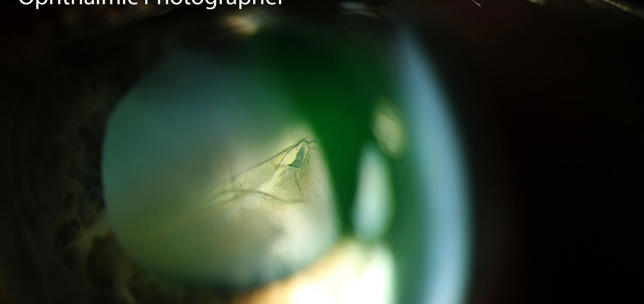

The ANTerior Segment Imaging Competition from Eye News and Keeler promotes and celebrates the work of slit-lamp imaging, culminating in cash prizes and exposure for its winners.

After a successful run in 2024, the ANTS Imaging Competition returned this year with another overwhelming response and our judges were thrilled to have so many amazing images to choose from. We would like to offer a huge congratulations to our winners, honorary mentions, and shortlisted entries, all of which can be seen below. So, without further ado, here some of the best ophthalmic imagers, optometrists and allied professionals in the UK right now: